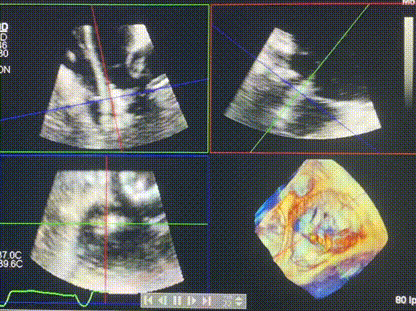

術(shù)后超聲顯示僅殘余微量瓣周漏

LuX-Valve Plus經(jīng)血管三尖瓣置換系統(tǒng)此次“出海”圓滿完成,術(shù)后Rodrigo Estévez-Loureiro教授對LuX-Valve Plus經(jīng)血管三尖瓣置換系統(tǒng)的器械性能和治療效果大為稱贊,認為LuX-Valve Plus的手術(shù)體驗非常好。術(shù)后即刻超聲顯示三尖瓣反流幾乎完全消失,血流動力學(xué)改善顯著,患者恢復(fù)快。在面對復(fù)雜解剖結(jié)構(gòu)、超聲影像質(zhì)量不佳、有起搏導(dǎo)線干擾時,Lux-Valve Plus也體現(xiàn)了極強的適應(yīng)性。Thomas Modine教授和Anson Cheung教授也肯定了LuX-Valve Plus術(shù)中操作的便捷性,認為LuX-Valve Plus容錯率高,對術(shù)中影像的依賴較小,后期希望可以更多的應(yīng)用LuX-Valve Plus三尖瓣置換系統(tǒng)于臨床實踐,讓更多的三尖瓣重度反流患者盡早獲益,改善預(yù)后。